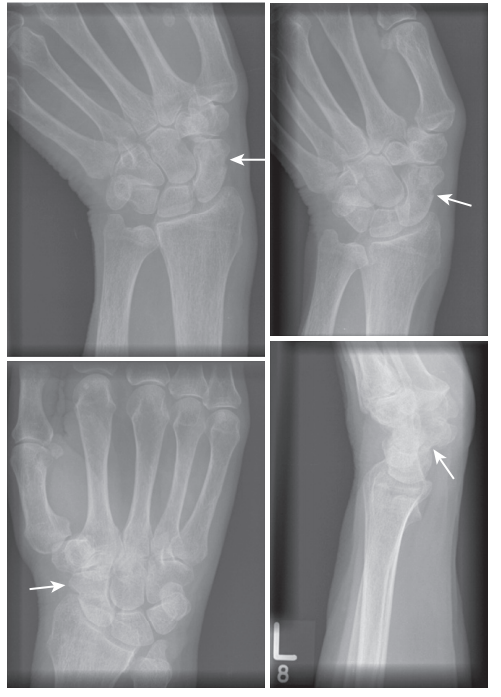

A patient has a fractured carpal bone in the floor of the anatomic snuffbox. Radiograph is attached. Which bone is fractured?

A

The anatomic snuffbox is formed by the tendons of the extensor pollicis brevis, the abductor pollicis longus and the extensor pollicis longus. The floor is formed by the scaphoid bone.